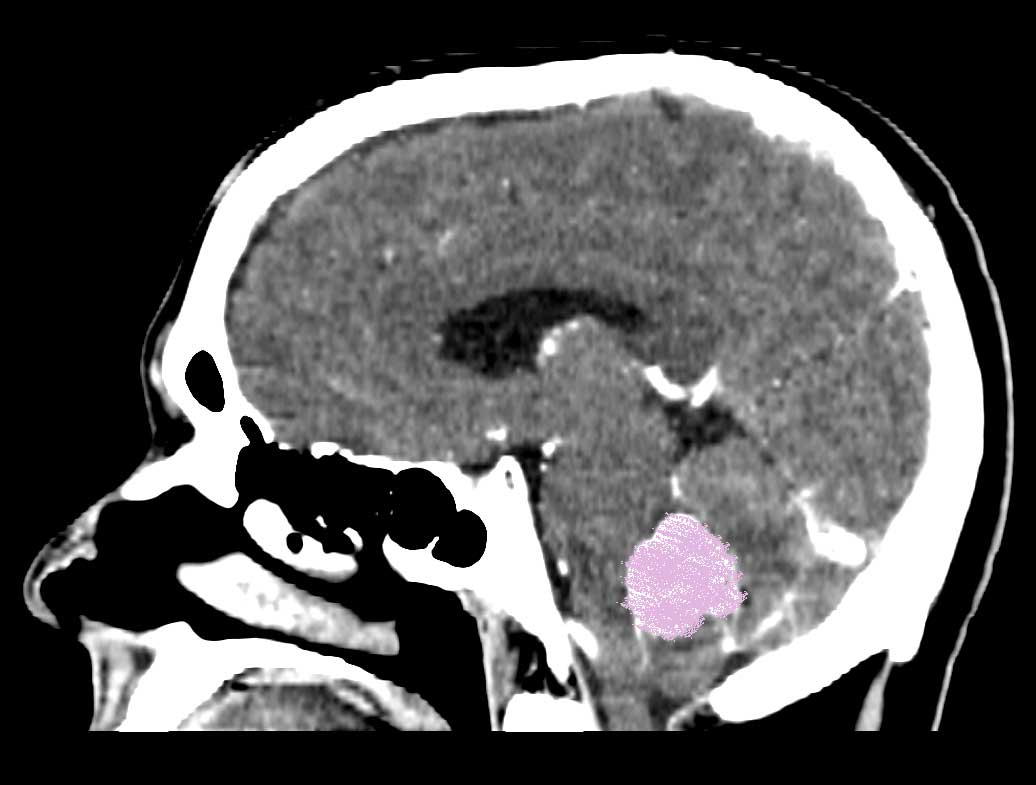

I was diagnosed with a Posterior Fossa tumor 10 days ago.

With that said, the tumor continues to press upon my brain stem and I am in bad shape.

(the lower image shows the Tumor pressing on the brain stem)

(the other white areas are cerebral fluid channels)